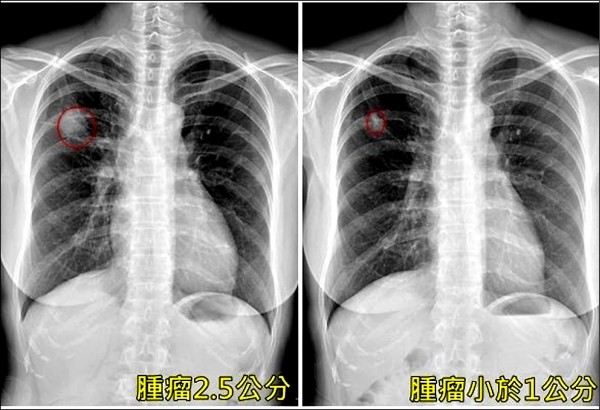

圖片來源:自由時報